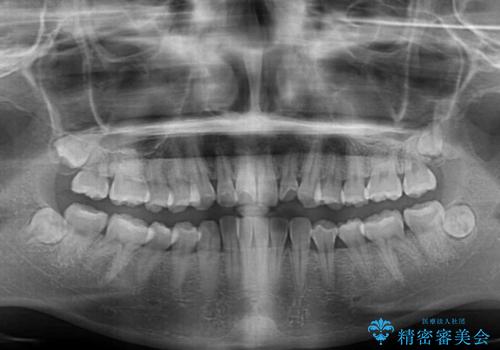

- 前歯の捻れを気にして来院された患者様です。

上顎前歯が捻れて前方に飛び出しており、下顎前歯もそれに沿うようにデコボコとなっていました。

IPR(歯と歯の間を削る処置)によりスペースを獲得して下顎前歯のデコボコを改善し、上顎前歯は下顎前歯と接する位置にまで引っ込めるように設定し、インビザラインにて矯正治療を行うこととしました。